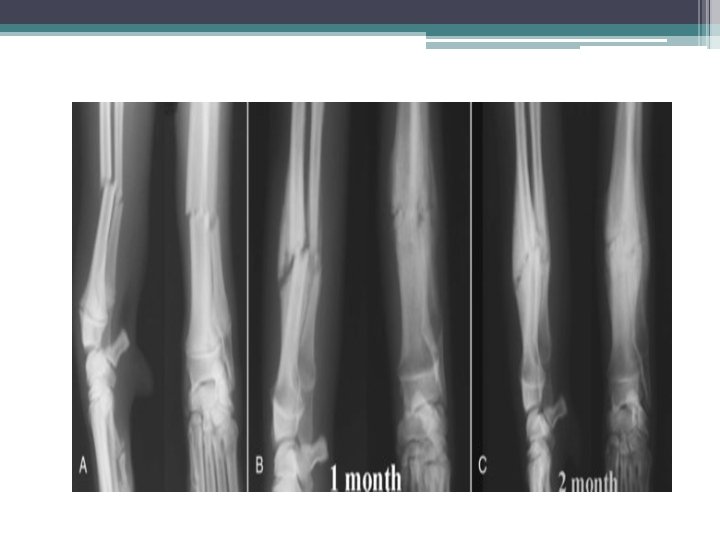

• 5 -Greenstick Fracture: : Incomplete fracture that usually occurs in children (the bone partly fractures on one side, but does not break completely because the rest of the bone can bend).

Greenstick fracture in the radius Greenstick fracture in the ulna